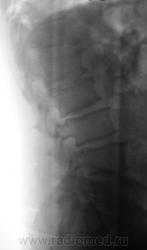

Пол пациента: Мужской пол Тип патологии: Другое Область исследования: Скелетно-мышечная система Методы исследования: Rg Пациент направлен на рентгенографию поясничного отдела позвоночника. https://radiomed.ru/sites/default/files/styles/case_slider_image/public/user/12/2.pb100007a.jpg?itok=U7NupSFv https://radiomed.ru/sites/default/files/styles/case_slider_image/public/user/12/3.pb100008.jpg?itok=uQAcfJjo https://radiomed.ru/sites/default/files/styles/case_slider_image/public/user/12/4.pb100008a.jpg?itok=HrnStjvs ID:8713 Thu, 11/11/2010 - 17:40 #1 Helios Offline Last seen: 8 months 4 days ago Joined: 06.08.2010 - 15:16 Posts: 4417 Остеохондроз, деформирующий спондилез и , кажется, spina bifida крестца. Thu, 11/11/2010 - 21:47 #2 Глазков Игорь А... Offline Last seen: 9 months 4 weeks ago Joined: 19.12.2008 - 20:41 Posts: 1597 spina bifida крестца. Узелки Шморля в 2,3,4 позвонках. Остеохондроз поясничного отдела позвоночника. Прийди к Себе Wed, 17/11/2010 - 17:19 #3 Сан Саныч1 Offline Last seen: 12 months 1 day ago Joined: 07.06.2010 - 21:17 Posts: 2114 И спондилолиз Л5 слева. Хочешь сделать что-то нормально - сделай это сам!

Остеохондроз, деформирующий спондилез и , кажется, spina bifida крестца.

spina bifida крестца. Узелки Шморля в 2,3,4 позвонках. Остеохондроз поясничного отдела позвоночника.

И спондилолиз Л5 слева.